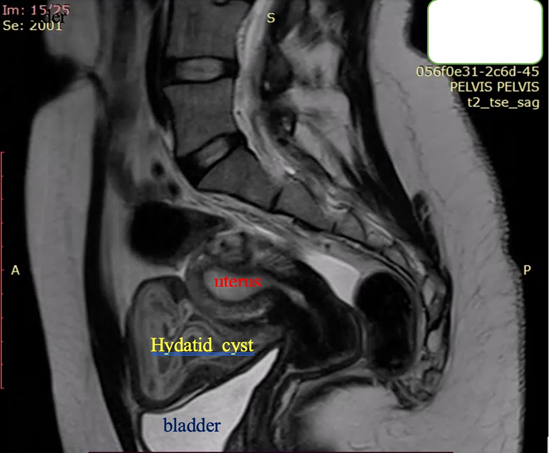

A 23-year-old asymptomatic female patient. During a routine gynecological examination, pelvic ultrasound identified a nonspecific tumor-like mass of solid consistency (Figures 1-3). The patient is sexually active and nulliparous. She has no history of abnormal menstrual bleeding or pelvic pain. Pelvic ultrasonography demonstrated a nonspecific tumor-like mass. The lesion was located in the vesicouterine space, anterior to the uterus (which was in anteversion and anteflexion with length 6.5 cm.) and posterior to the urinary bladder. The mass measured approximately 10 cm and had a predominantly solid component, with multilaminar hypoechoic bands within its capsule (Figures 1 and 4). Both ovaries were visualized and appeared normal on transvaginal ultrasonography (Figures 2 and 3). The pouch of Douglas is free of fluid.

Figure 7. Sagittal T2-weighted MRI: Bright hyperintensity, multiple cystic formation in the small pelvis, located retro-vesical and in contact with the uterus, with internal zones compatible with “daughter” cysts.